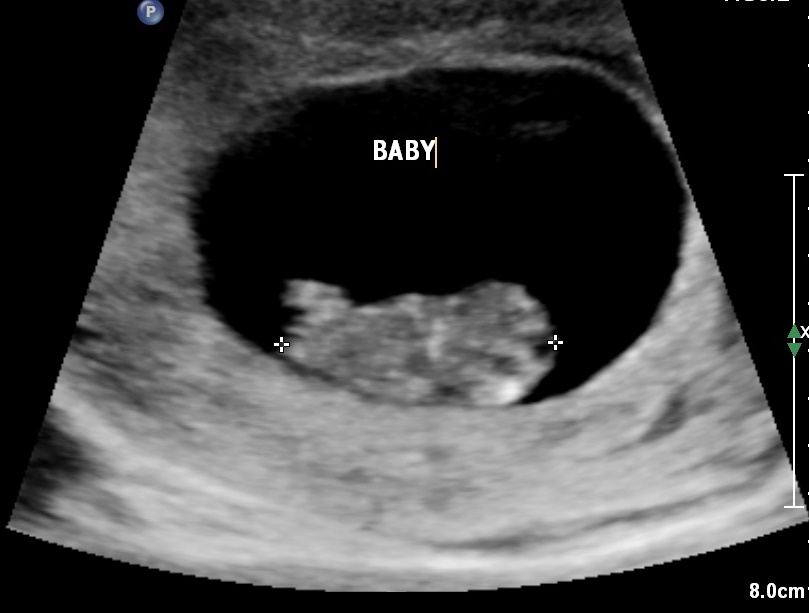

DH and I had a wonderful first appt today! I am currently 9w5d. We got to have a long in depth convo with my ob about screenings, waht to expect for her and the practice, and all the fun that awaits! I was somewhat disappointed that they didn't plan to do an ultrasound, but when I expressed how anxious I was to hear the heartbeat, they made quick arrangments for DH and I to head over and get the us right away! The best news of the week is that little bug is measuring right on target with a heartbeat of 181! It was magical.

We had our 12 week appt today and I thought it we were just going to hear the heartbeat. Ob surprised us by doing an US saying they are more fun! So we got to see the sweet baby flipping and stretching. We also heard the heartbeat (154)!!!

• 12 week appointment and NT scan. Baby was moving all over the place and had a heartbeat of 164. Dr says measurements look great just have to wait on the blood work. So glad to be over the 12 week mark!

• Had my appointment for the verify screening and check up since i am high risk. Very emotional appointment. When i lost one of mine on 4/1/13 they went to listen to the heart rate on the doppler and didnt find the heart beat then did an ultrasound and baby didnt make it. Today on 11/21/14 she went to listen to the heart with a doppler and there wasnt a heart beat so of course i balled my eyes out as she ran out of the room to grab an ultrasound machine. When she came back she found baby and heart was perfect had arms, legs perfect head everything. So happy i have made it past another milestone. Cant wait for the results of the Verify test to make sure we are in the clear of other risks. Happy pregnancy to all you ladies.

• Had 12 week appt today. Couldn't hear heart beat on Doppler so she snuck in a quick ultrasound! It was great to see baby moving like crazy. Great appt.

• Had my first ultrasound today I *thought* I was 10 weeks, but am actually 9 weeks which threw me for a loop, but as I have experienced a loss the US put my mind at ease. Strong heartbeat for my little one. :):)

• 9 wk 5 day for me too today... Awesome seeing it move and seeing the heartbeat. I did find out I have a tilted uterus... Which I guess is not a big deal but will be waiting and hoping for the natural correction in the next weeks.